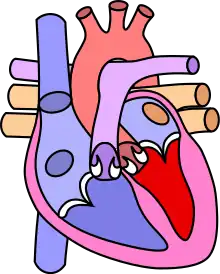

Diagram of a healthy heart and one with tetralogy of Fallot

Heart with tetralogy of fallot A: Pulmonary stenosis; B: Overriding aorta; C: Ventricular septal defect (VSD); D: Right ventricular hypertrophy

Normal heart